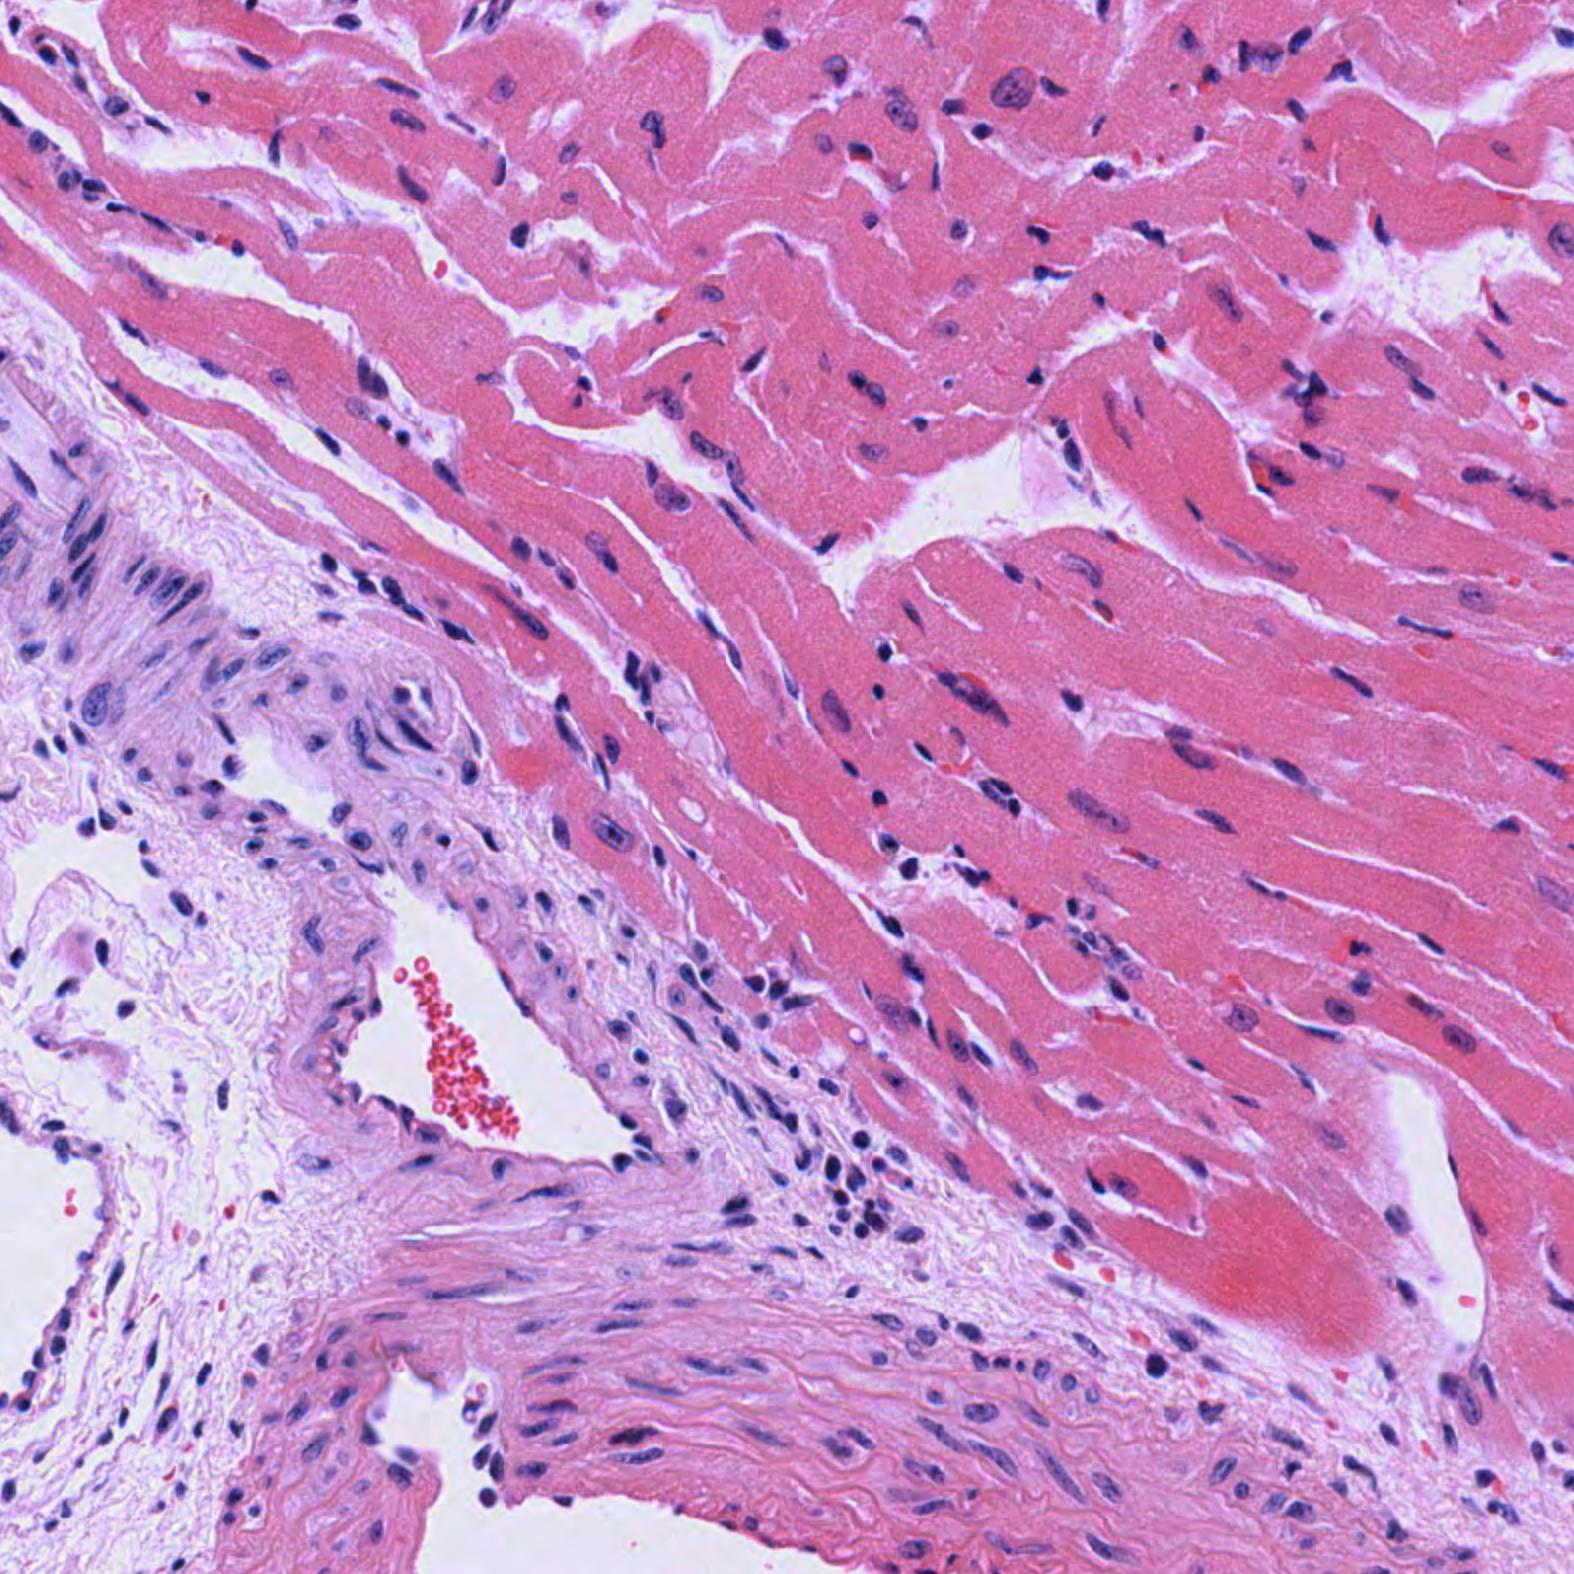

| Heart_H&E_02.svs Heart_H&E_02.png |